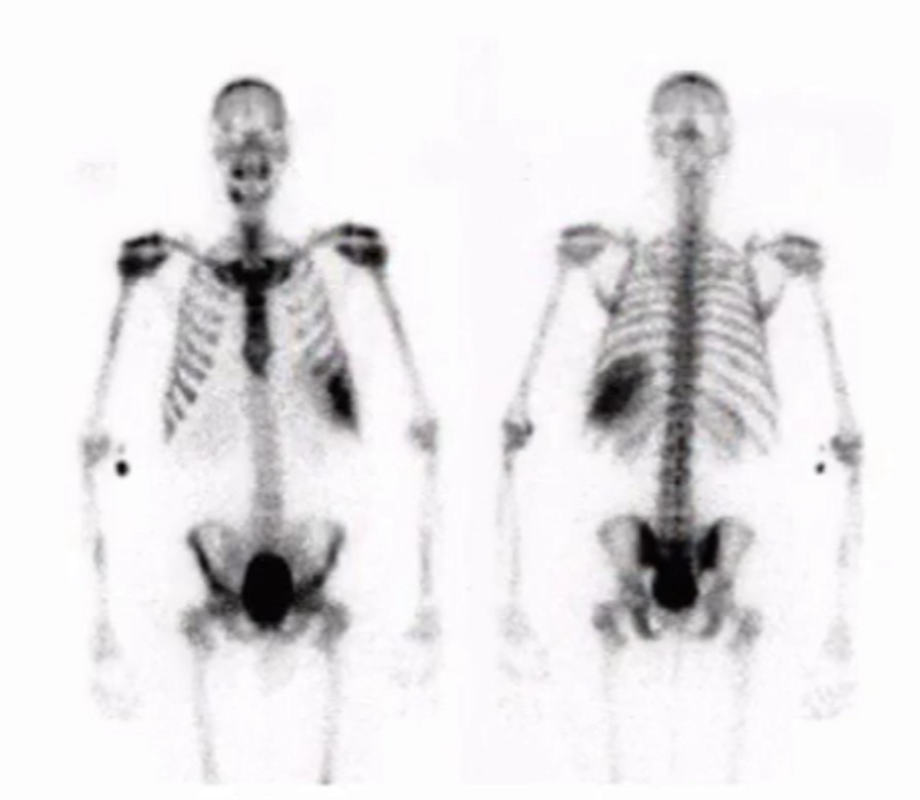

Hypertrophic Osteoathropathy

• Look at shins and you will see linear areas of high uptake along periosteum

• Called tram tracking

• Next step - likely CT chest for lung cancer eval

• Other DDx:

• Hypoxia, cyanotic heart disease, pulmonary pathology